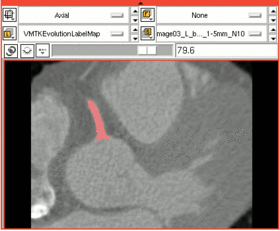

| Segmentation of the vessel lumen can be performed using the VMTKEasyLevelSetSegmentation module. The level-set segmentation process consists of two steps: Fast Marching Upwind Gradient initialization ([Antiga2008], [Sethian1999]) and Geodesic Active Contours evolution ([Caselles1995]).

The initialization step involves the description of a starting model within a region of interest. In the evolution step this initial deformable model then gets inflated to match the contours of the targeted volume. We want to initialize inside the RCA on the vessel enhanced volume from the previous step and then evolve on the original extracted subvolume. INSTRUCTIONS: Initialization:

The initial segmentation is shown as an overlayed labelmap in the 3D Slicer slice viewers and a red model is shown in the 3D rendering window. Evolution:

The evolved segmentation is shown as an overlayed labelmap in the 3D Slicer slice viewers and a blue model is shown in the 3D rendering window. |

For the segmentation of the RCA we use the following parameters:

Attraction to ridges is the most important parameter. Since our initialization is already pretty good, we only choose medium inflation and medium curvature. The Fast Marching initialization takes some time. Our extracted subvolume gets processed in about 6 minutes on a Quad Core 2.6GHz Xeon machine with 6GB of RAM.